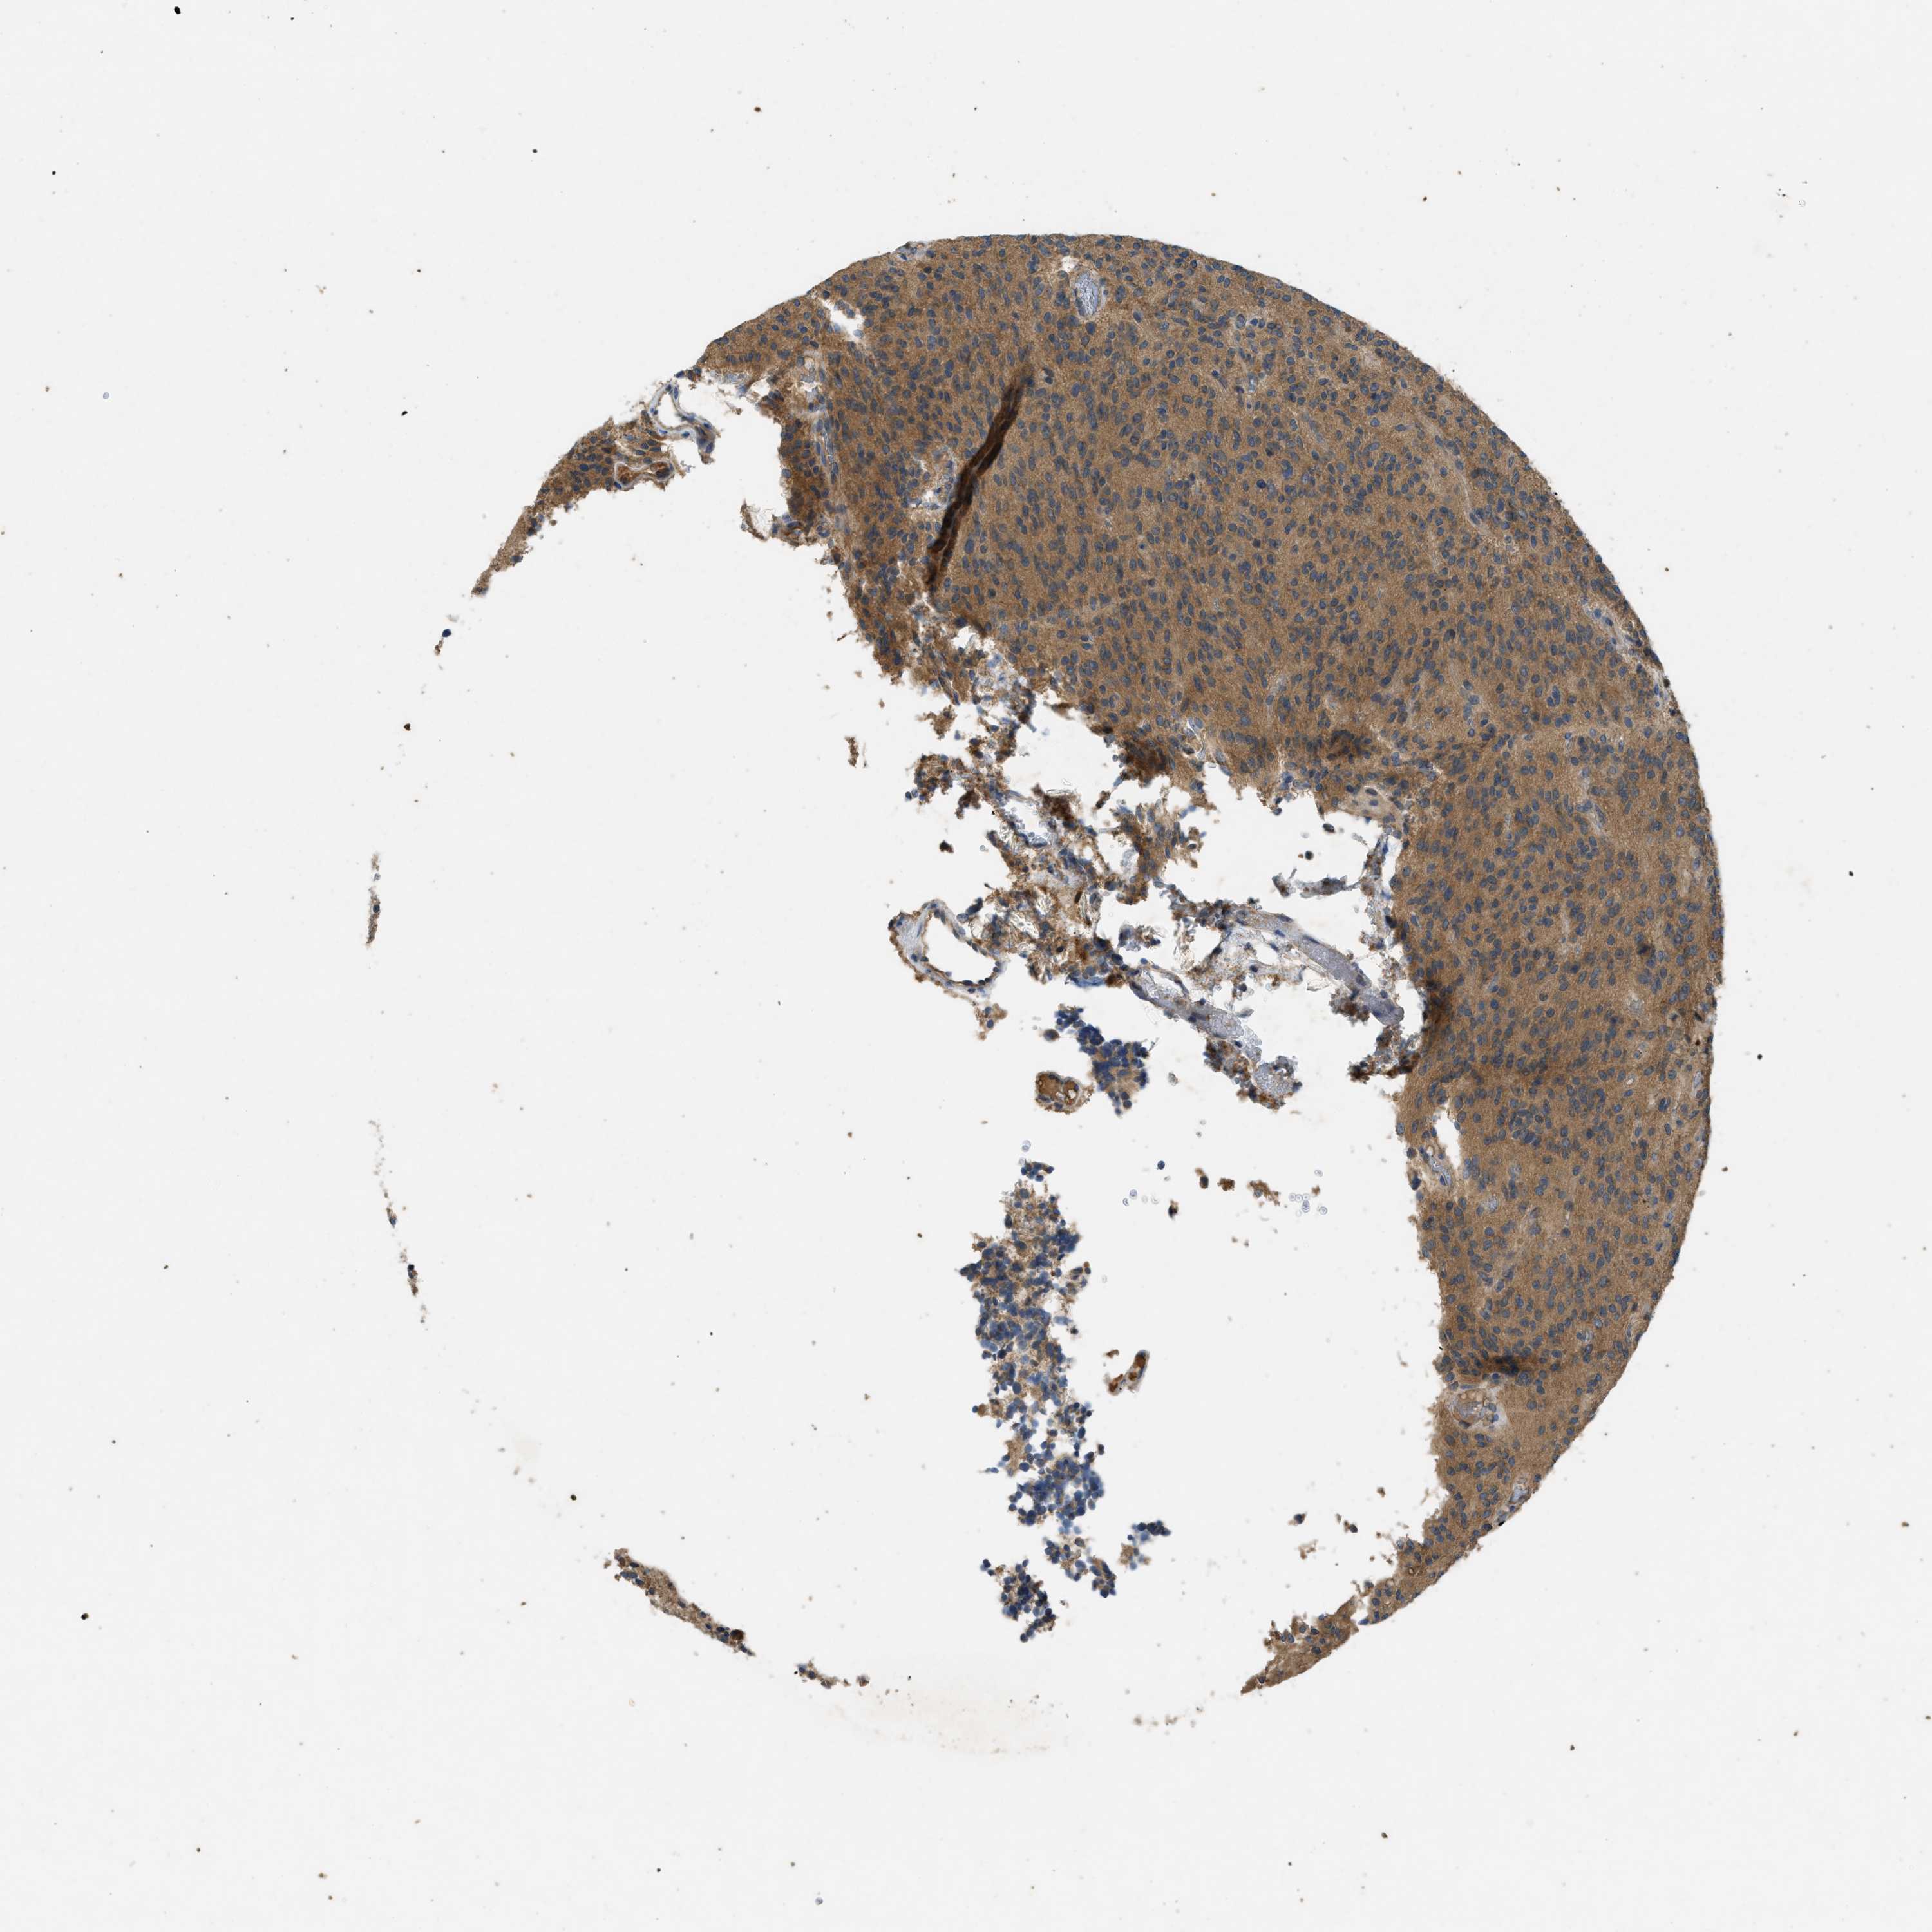

GLIOMA - Protein expressioni

A mouse-over function shows sample information and annotation data. Click on an image to view it in a full screen mode. Samples can be filtered based on level of antibody staining by selecting one or several of the following categories: high, medium, low and not detected. The assay and annotation is described here.

Note that samples used for immunohistochemistry by the Human Protein Atlas do not correspond to samples in the TCGA dataset.

Antibody stainingi

Antibody staining in the annotated cell types in the current human tissue is reported as not detected, low, medium, or high, based on conventional immunohistochemistry profiling in selected tissues. This score is based on the combination of the staining intensity and fraction of stained cells.

Each image is clickable and will lead to virtual microscopy that enables deeper exploration of all samples and also displays staining intensity scores, fraction scores and subcellular localization as well as patient and tissue information for each sample.

Antibody HPA012778

Antibody CAB018581

Staining

High

Medium

Low

Not detected

Intensity

Strong

Moderate

Weak

Negative

Quantity

>75%

75%-25%

<25%

None

Location

Nuclear

Cytoplasmic/membranous

Cytoplasmic/membranous,nuclear

Glioma, malignant, High grade

Glioma, malignant, Low grade